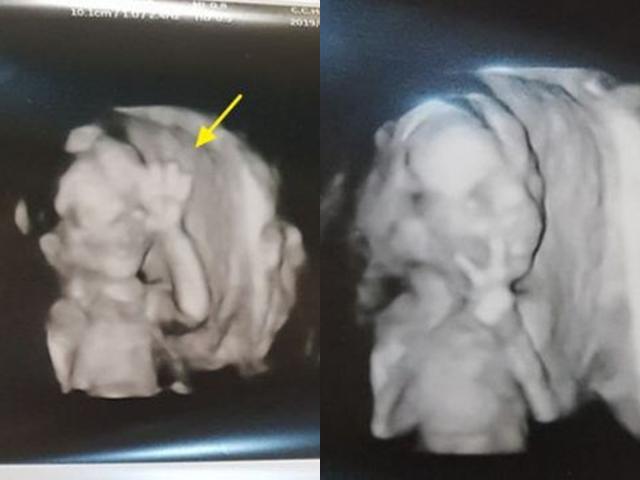

Người mẹ hạnh phúc kể lại rằng vào tuần thai thứ 24, chị đã cùng chồng đi siêu âm để kiểm tra sức khỏe thai nhi. Bác sĩ đã đưa máy siêu âm đi quanh bụng chị Jodie để hai vợ chồng có thể xem toàn bộ cơ thể đứa con. Đó cũng là lúc họ nhận ra một điều vô cùng thú vị ở bàn tay của con gái.

Bé gái giơ tay giống biểu tượng "quẩy lên, vui lên đi".

"Khi bác sĩ siêu âm, con gái tôi đã lấy tay che toàn bộ khuôn mặt, vì vậy tôi đã thử chọc vào bụng mình rồi nói: 'Con có thể chỉ cho bố mẹ biết rằng con vẫn ổn được không?'. Ngay sau lời nói đó, con bé đã đưa tay lên rồi làm hành động hết sức dễ thương", chị Jodie nói. Bé gái trong bụng chị đã giơ hai ngón tay trỏ và út lên giống hệt như biểu tượng "quẩy lên, vui lên đi" mà giới trẻ hiện nay hay sử dụng.

Hành động này của bé gái đã khiến chị Jodie và anh Davie sốc nặng. Ngay cả các bác sĩ cũng bất ngờ trước "thần giao cách cảm" quá đặc biệt của hai mẹ con. "Ngay khi nhìn thấy bàn tay của con, chúng tôi đã nghĩ con là điều tuyệt nhất mà chúng tôi có. Chúng tôi yêu con rất nhiều", chị Jodie chia sẻ.